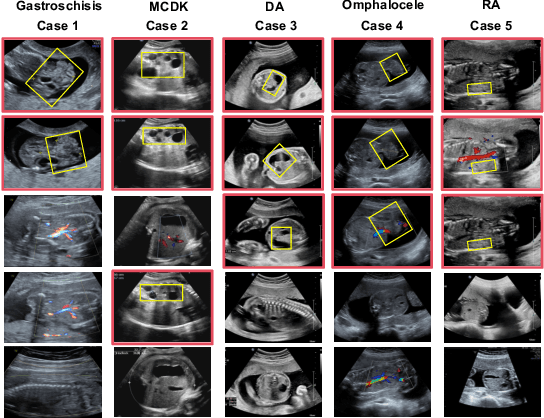

Abstract:Fetal abdominal malformations are serious congenital anomalies that require accurate diagnosis to guide pregnancy management and reduce mortality. Although AI has demonstrated significant potential in medical diagnosis, its application to prenatal abdominal anomalies remains limited. Most existing studies focus on image-level classification and rely on standard plane localization, placing less emphasis on case-level diagnosis. In this paper, we develop a case-level multiple instance learning (MIL)-based method, free of standard plane localization, for classifying fetal abdominal anomalies in prenatal ultrasound. Our contribution is three-fold. First, we adopt a mixture-of-attention-experts module (MoAE) to weight different attention heads for various planes. Secondly, we propose a medical-knowledge-driven feature selection module (MFS) to align image features with medical knowledge, performing self-supervised image token selection at the case-level. Finally, we propose a prompt-based prototype learning (PPL) to enhance the MFS. Extensively validated on a large prenatal abdominal ultrasound dataset containing 2,419 cases, with a total of 24,748 images and 6 categories, our proposed method outperforms the state-of-the-art competitors. Codes are available at:https://github.com/LL-AC/AAcls.